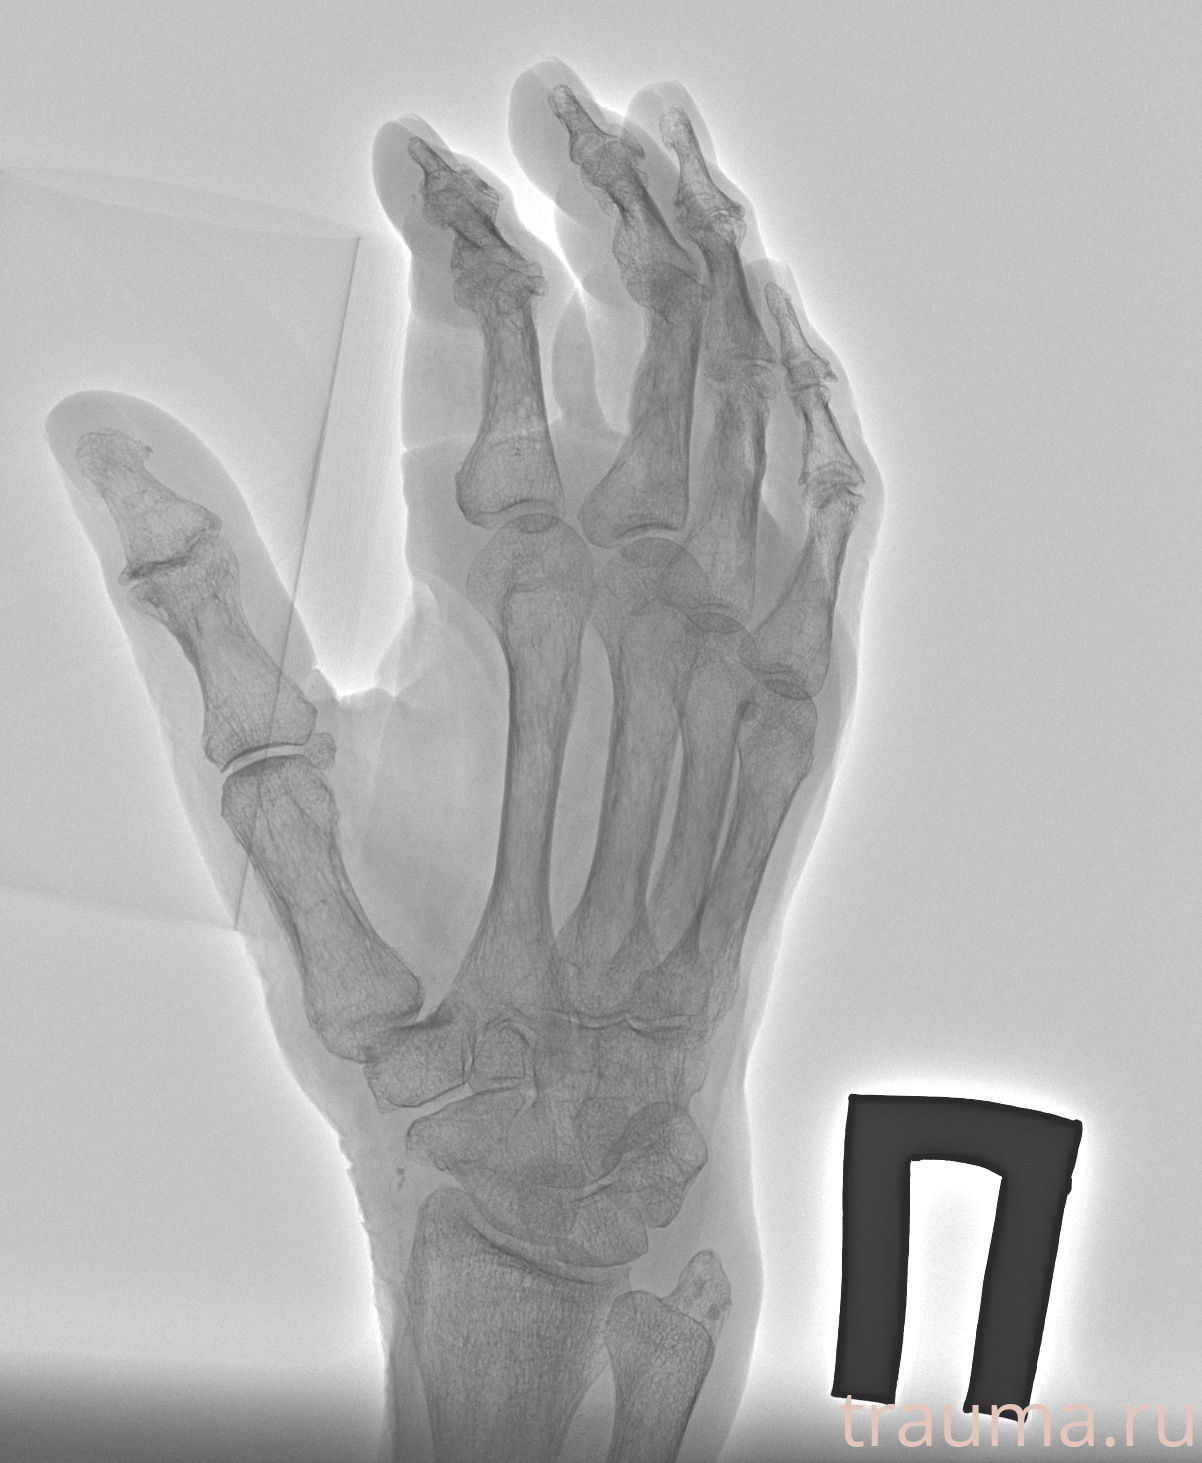

Рентгенограммы

Рентген на дому: по вашему адресу приезжает врач-рентгенолог, травматолог-ортопед с мобильным рентгеновским аппаратом, проводит диагностику травмы или заболевания, делает необходимые рентгенограммы, дает рекомендации по дальнейшему лечению. Получить качественные снимки в домашних условиях возможно благодаря уникальной методике, разработанной МосРентген Центром для института  Склифосовского